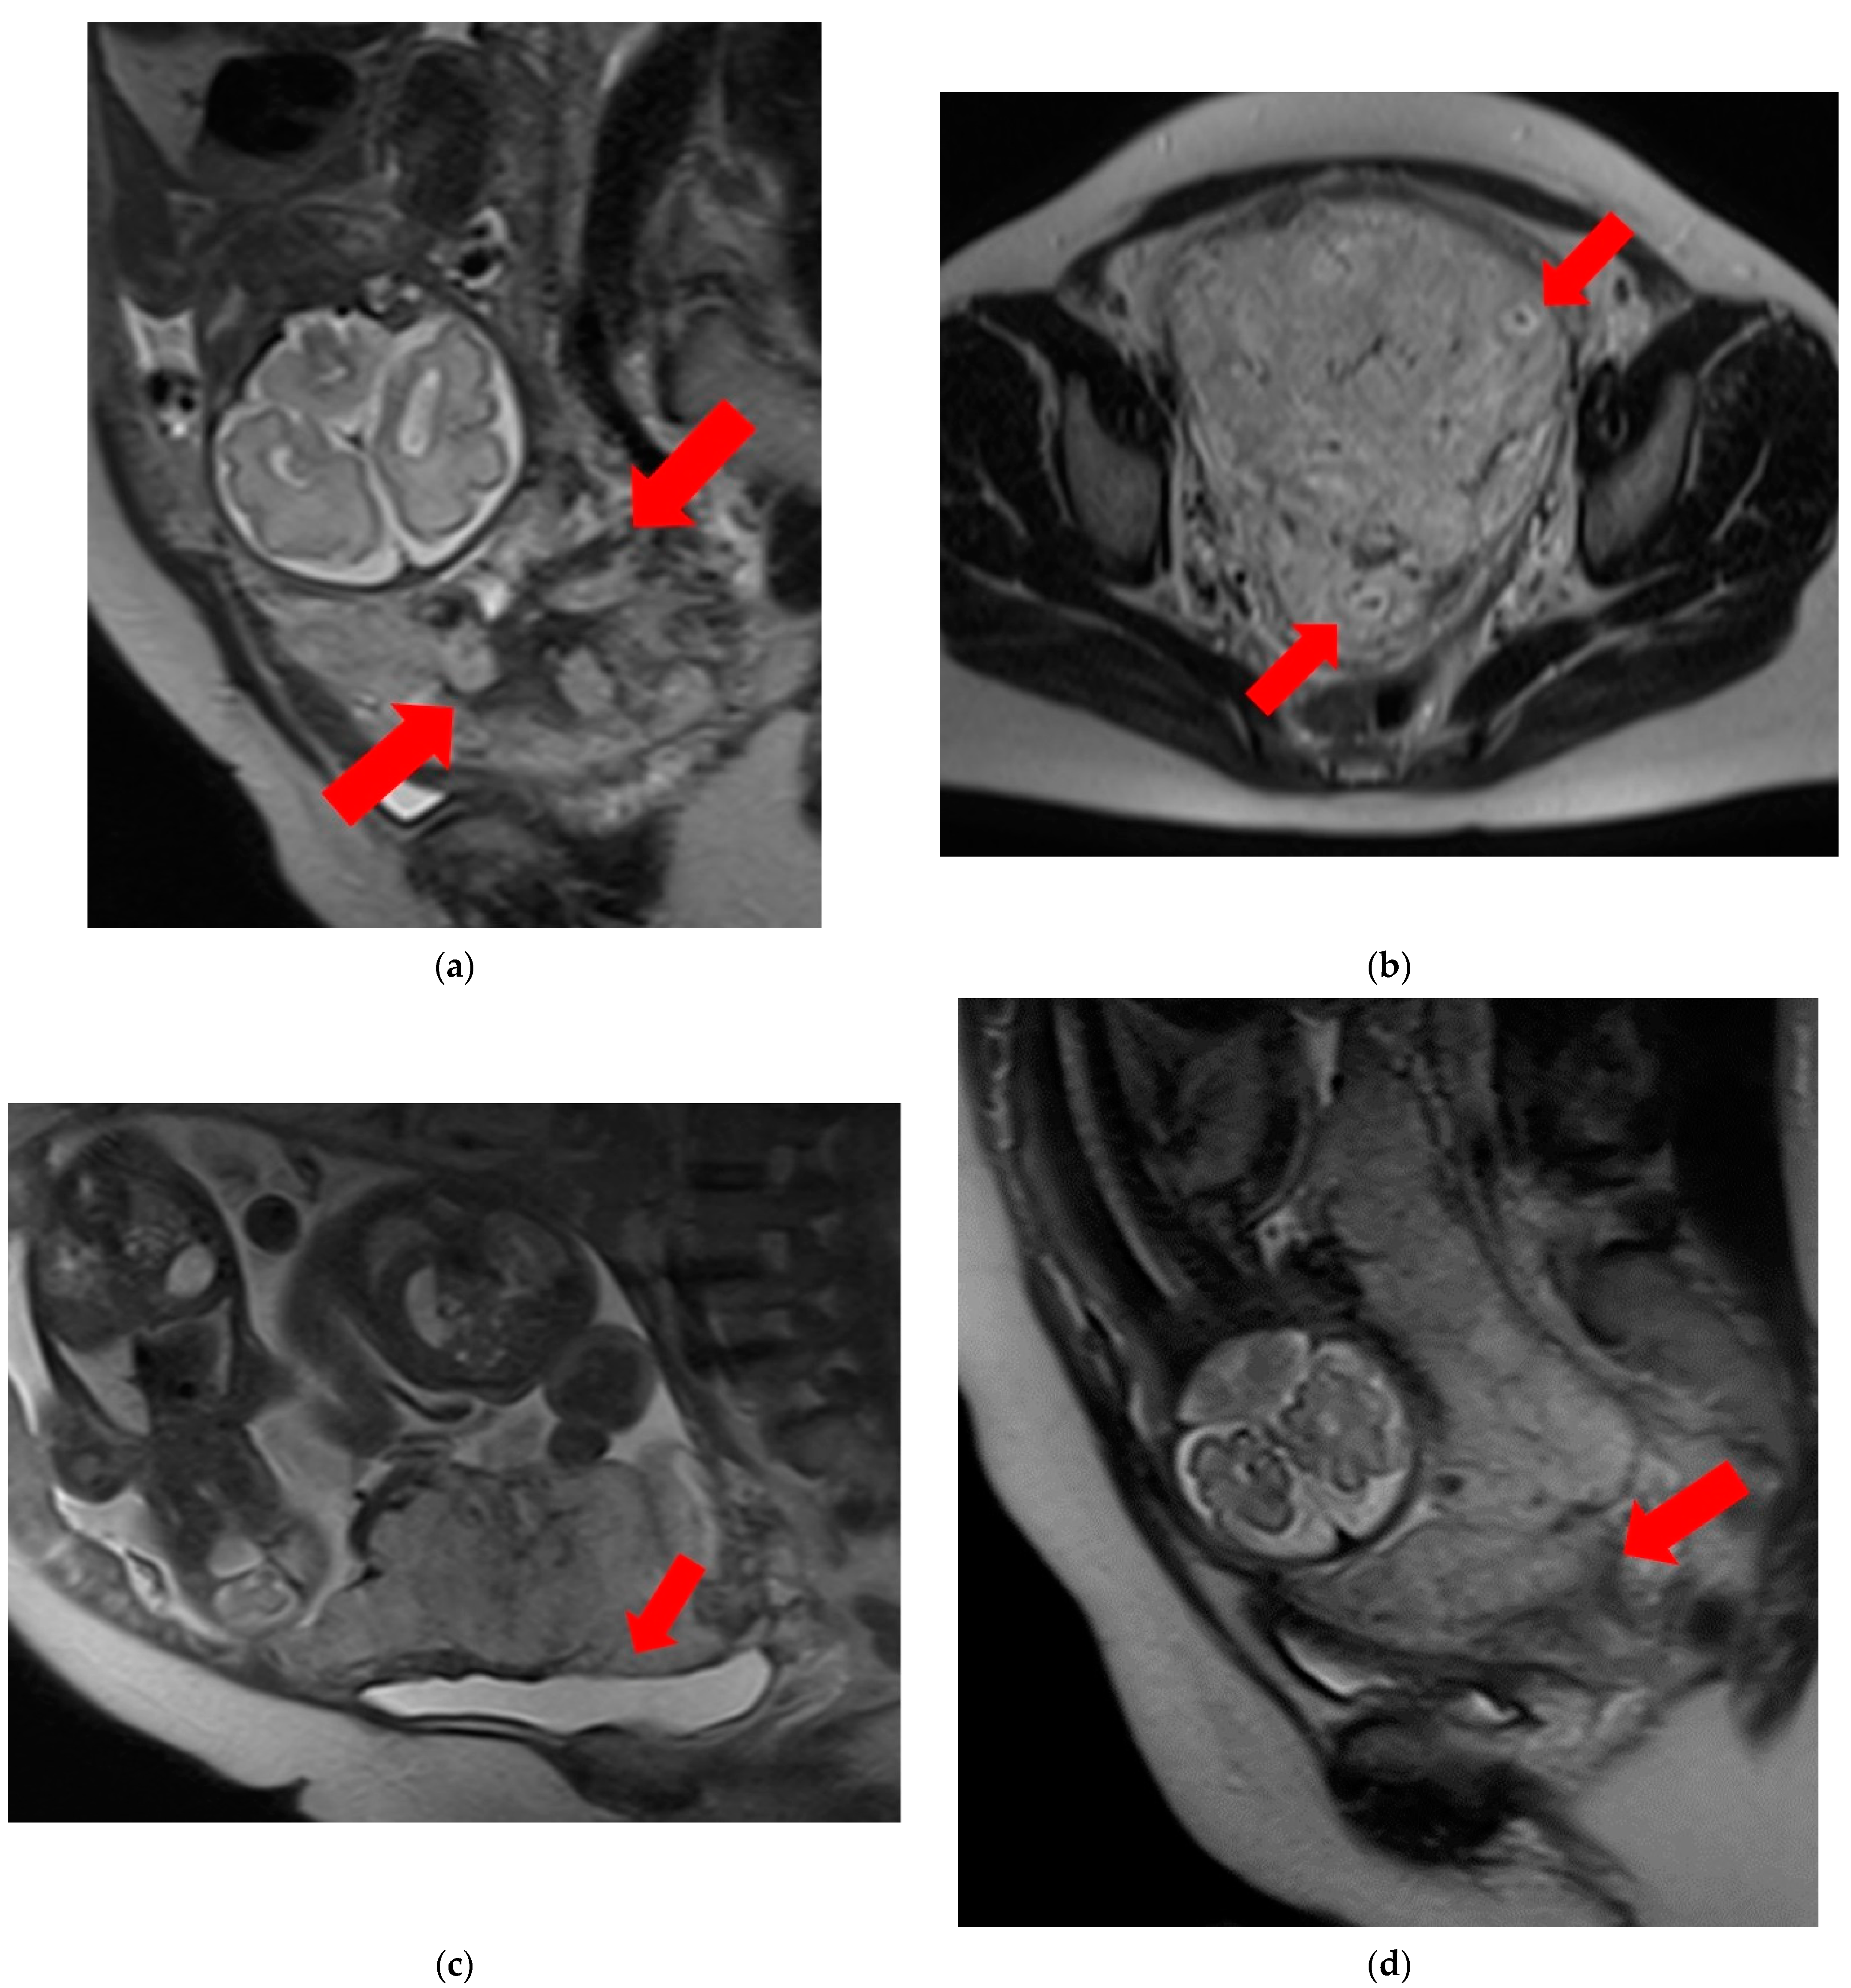

2.5. Imaging Analysis and Assessment of MRI Features of PAS Disorders

Blinded to the clinical and pathological findings after treatment, two experienced radiologists (with 9 and 15 years of experience, respectively) independently examined the MR images. Seven MRI features suggestive of PAS disorders were evaluated for the presence or absence of the following: T2 dark bands, placental heterogeneity, placental bulge, placental cervical protrusion sign, abnormal vascularization of the placental bed, focal exophytic mass, and myometrial thinning [7,9].

• T2 dark bands: dark lines on T2-weighted images showing nodular or linear patterns from the uterus to the placenta (Figure 1a).

• Placental heterogeneity: uneven signal intensity observed inside the placenta, often due to repeated bleeding (Figure 1b).

• Placental bulge: lower uterine protrusion caused by the placenta, usually toward the bladder (Figure 1c).

• Placental cervical protrusion sign: placental tissue sticking to the cervical canal (Figure 1d).

Figure 1. Examination of magnetic resonance imaging features in the spectrum of placenta accreta with placenta previa disorder reveals the following characteristics: (a) T2 dark bands, indicating areas of low signal intensity on T2-weighted images (arrows). (b) Placental heterogeneity, depicting varied signal intensity within the placenta due to recurrent hemorrhages or lacunae (arrows). (c) Placental bulge, characterized by the protrusion of the lower segment of the uterus caused by the mass effect of the placenta, typically towards the bladder (arrow). (d) Placental cervical protrusion, showcasing the extension of placental tissue into the cervical canal (arrow). (e) Abnormal vascularization of the placental bed, featuring noticeable vessels in the placental bed with disruption of the uteroplacental interface (arrows). (f) A focal exophytic mass, indicating the protrusion of placental tissue through the uterine wall and beyond (arrows). (g) Myometrial thinning, demonstrating a reduction in myometrial thickness over the placenta to <1 mm or even making it invisible (arrow).